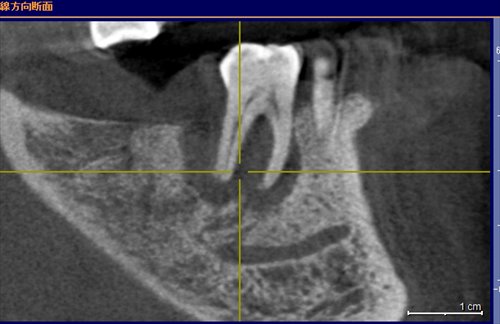

初診のレントゲン:歯の根っこの回りの黒いところはすべて膿。そりゃーお父さん揺れますよ、咬めませんよ。。。。。

本日。黒い所の変化に注目です!!骨の再生が!揺れもなくなり噛めるとの事。鯵を頭から食べたいと今日しきりに言っていました。まだまだ安定とはいえませんが治癒傾向である事は確かだと思います。